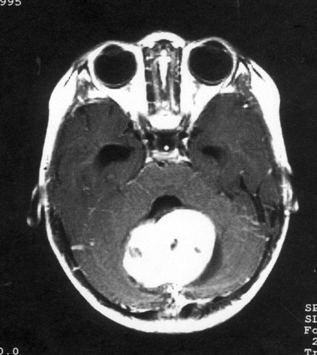

问题 病历摘要:??患儿男性,11岁。半年前开始出现行走不稳,常无故跌倒。半月前出现发作性剧烈头痛,伴恶心呕吐。体检:T36℃,P100次/分,R22次/分,BP100/60mmHg,神清,言语较缓慢,双眼外展约不及边,双眼侧视时有小幅度水平眼震。四肢肌力正常,右上肢肌张力较低,坐位姿势不稳,常不自主摇晃,双上肢指鼻不准,行走蹒跚步态,足距扩大,身前倾。 初步诊断考虑哪些疾病?提示:患儿行头颅?MR检查(见图)

选项 A.室管膜瘤 B.转移瘤 C.淋巴瘤 D.髓母细胞瘤 E.血管网状细胞瘤 F.星形细胞瘤 G.脉络丛乳头状瘤 H.多形胶质母细胞瘤

答案 ADFG